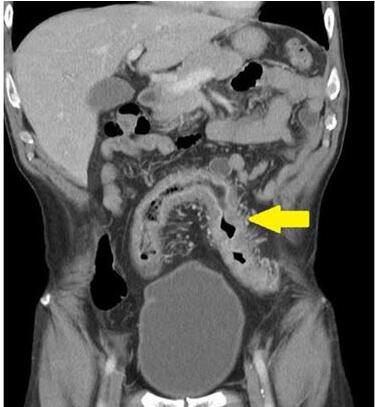

目前评估及后续监测病患肠道发炎情形,临床上可以透过如抽血检验白血球、发炎指数,或是合并粪便中钙卫蛋白的自费检测来定期追踪,不过最直接的方式是内视镜检查,大肠镜可以看到大肠黏膜,判断是否有溃疡性结肠炎或克隆氏症;克隆氏症有时会侵犯小肠,此时必须藉助小肠镜或胶囊内视镜来确定诊断。